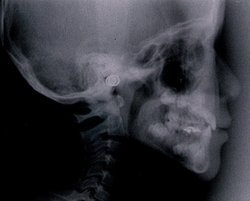

次に骨格で比べてみましょう。

同じ患者様の矯正治療終了後の骨格です。

不安定に見えていた咬み合わせが、反対咬合が改善されて安定して咬みあっていることが分かります。小学校低学年の治療であれば早期治療により反対咬合は容易に改善可能で、骨格の変化を考えてみても反対咬合は早期治療の効果が得られやすい症例と言えます。

7歳 初診時 女子の受け口の骨格

7歳 治療終了時 女子の受け口の骨格です。

同じ人の1年後の骨格です。

小学校低学年の治療であれば、この変化は普通に起こる変化です。

骨格のことからも受け口は早期治療の効果が得られやすい症例です。